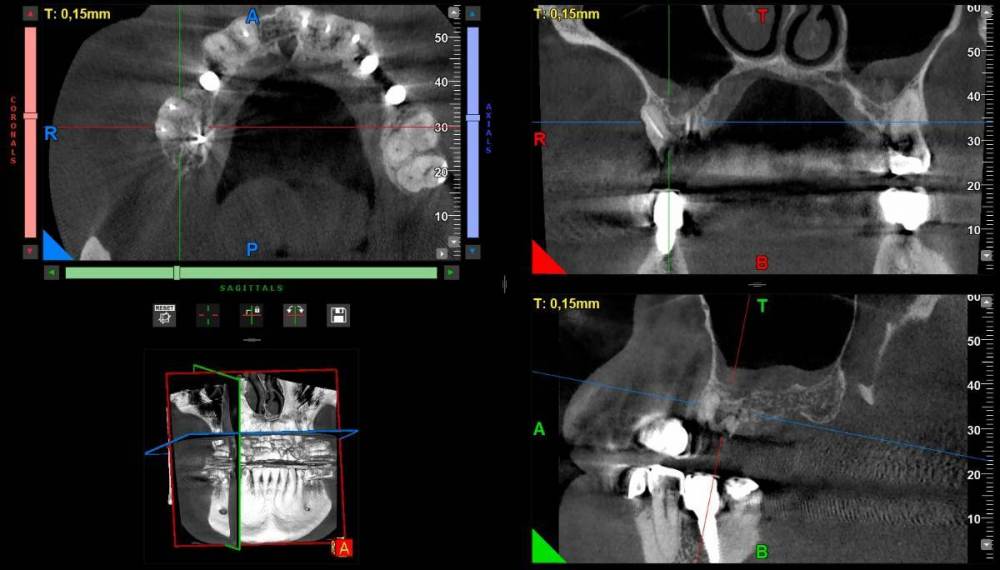

3. По поводу результатов проведенной имплантации 7 лет назад.  Один хирург  который смотрел мой снимок недавно выразил мнение, что импланты на верних челюстях выбраны избыточной длины и можно было просто поставить импланты большего диаметра и короче. Он увидел признаки резорбции кости.  Хотел бы услышать ваше мнение об этом и на сколько прав он в своих суждениях. Сколько лет еще могут простоять установленные импланты ? Про врачебную этику и пациентов знаю, но мы не раскрываем имя доктора, а если не хотите писать открыто можно написать мне в личку.  Для меня это очень важно. К доктору я естественно без претензий, но на выбор для новых операции безусловно повлияет.  Спасибо большое за то, что вы  прочитали и ваше мнение!

Компьютерная томография: https://cloud.mail.ru/public/nnZJ/N2pid2KKF

1. Зуб 16 удалять вне всяких сомнений. Закрытый или открытый синус-лифтинг? Решение будет принимать хирург, который будет вас оперировать.

3. Высказывания консультанта остаются на его совести. На мой взгляд, особо придраться не к чему. Хотя, "докопаться" и до столба можно.